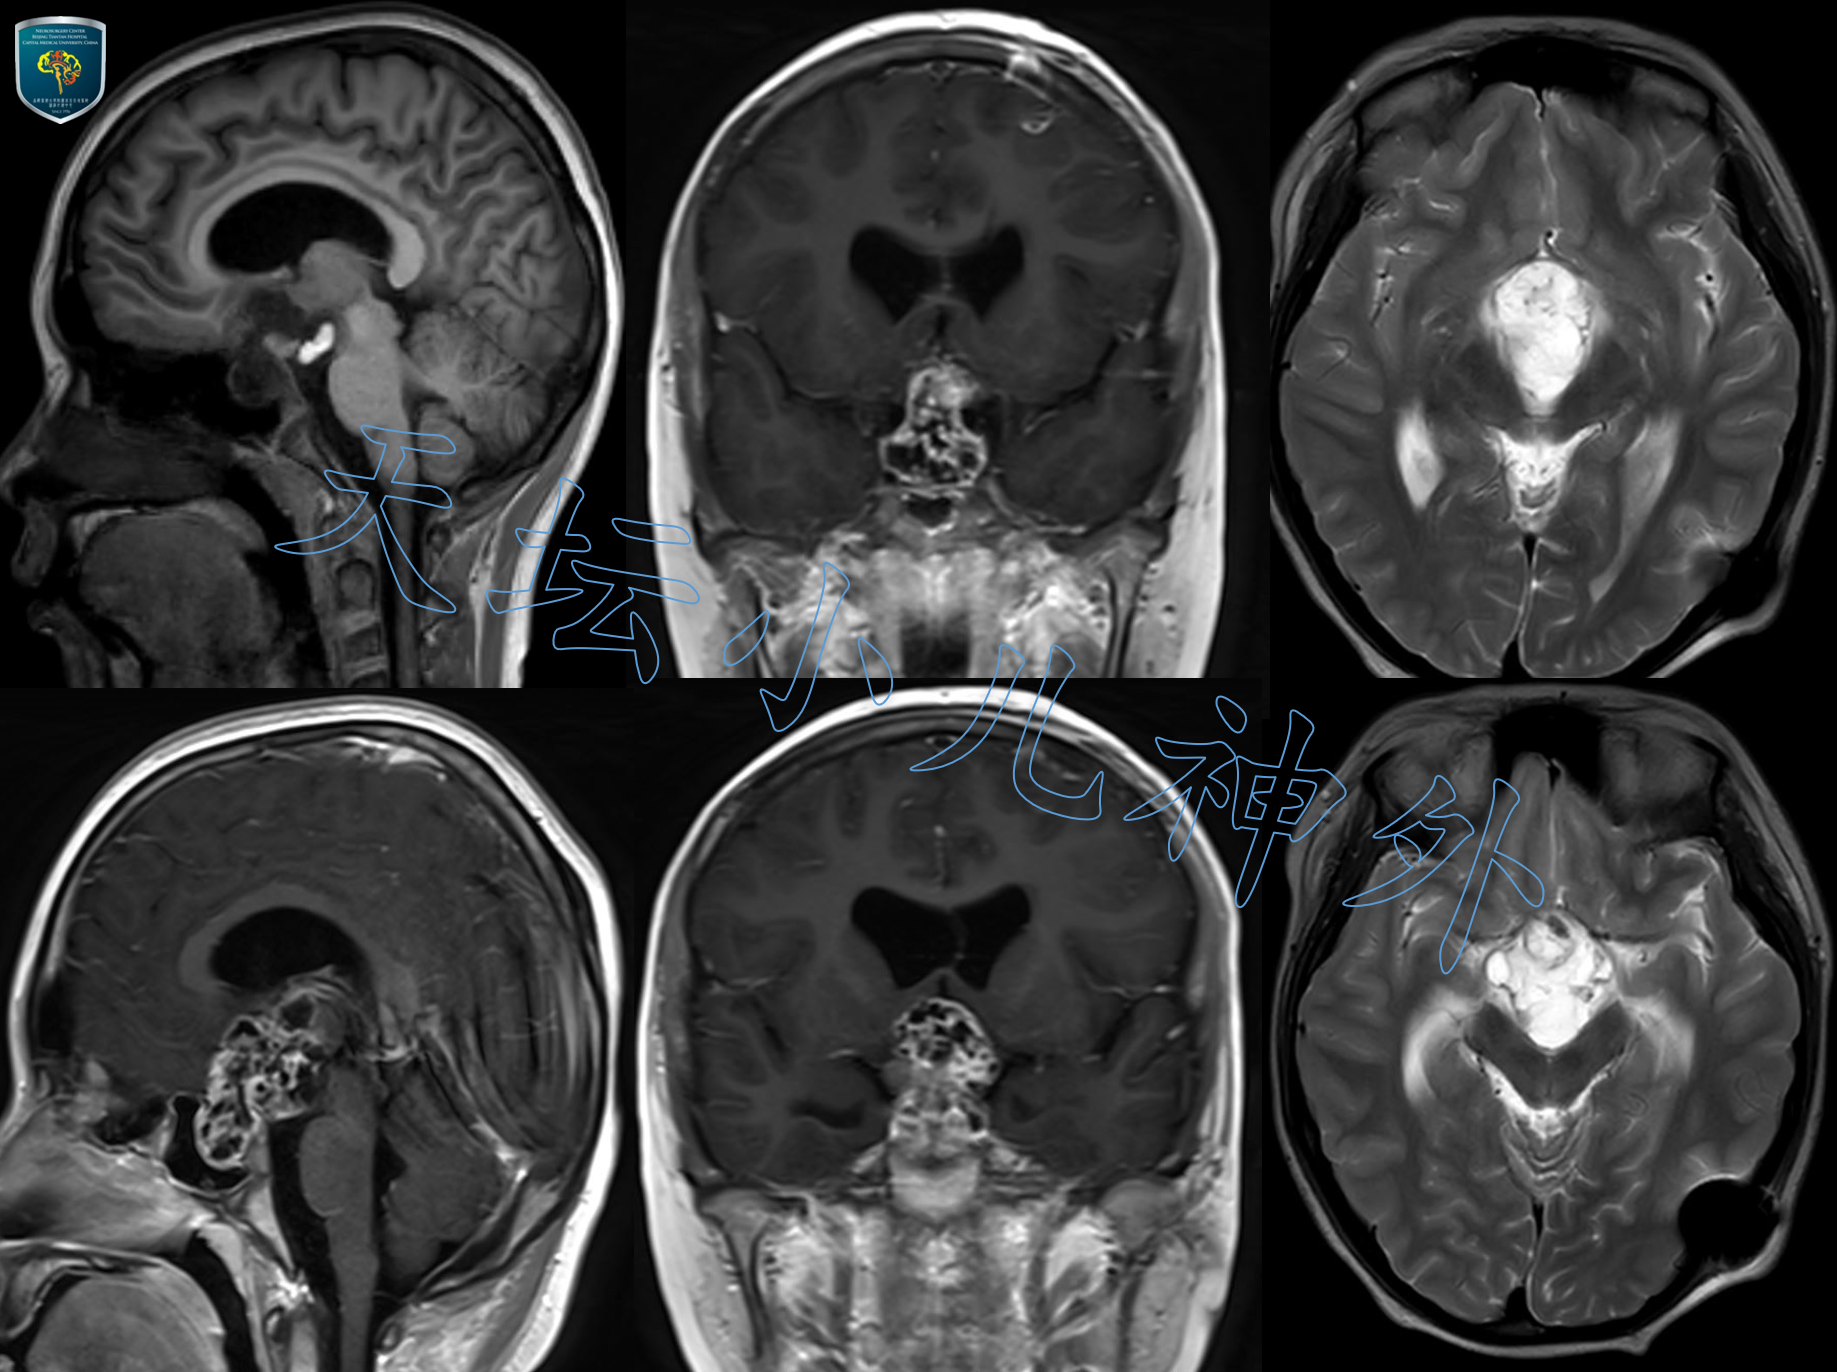

2020年8月接诊一例来自河北省唐山的12岁男性患儿(165cm,56kg)。患者主诉:间断性头痛伴呕吐3天,加重1天。查体示:生长发育基本正常;血清学提示肿瘤标记物阴性;激素水平基本正常;头颅CT/MRI示:鞍内、鞍上、三脑室区、鞍背后方巨大占位;颅咽管瘤可能性大。该病例系鞍区实体性肿瘤,非典型囊性瘤体伴蛋壳样钙化,需与视路胶质瘤、鞍区生殖类肿瘤相鉴别。鉴于首发症状无尿崩表现,肿瘤标记物阴性,MRIT1像出现脂类信号,基本除外生殖类肿瘤;患儿首发症状与视力无关,查体无水平眼震,MRI呈含脂类的混杂信号,视路胶质瘤可能性小。初步诊断为颅咽管瘤,且由于实体为主,难以植入Ommaya囊穿刺放液,只能考虑直接手术切除。

图1.术前MRI示鞍区占位,蝶窝明显扩大,肿瘤由鞍内、鞍上突入第三脑室。